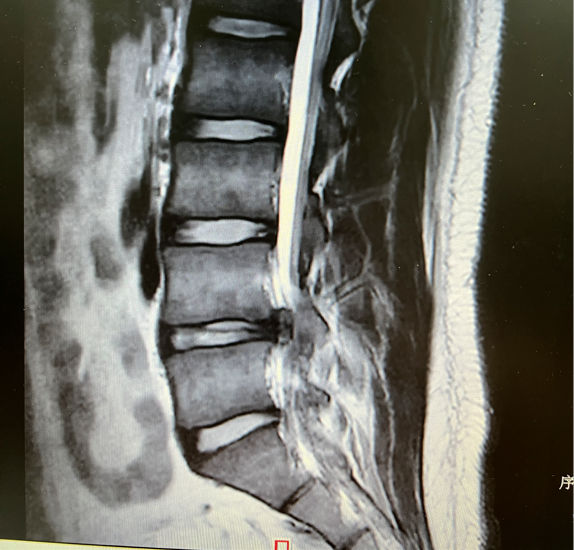

术前

骨科汪洋主任看了他的检查报告,发现他的腰椎间隙长出了一块面积较大的“阴影”,已经对神经造成了压迫。汪主任介绍,这是腰5骶1部位的椎间盘突出,小张的增生已经很严重了。

IMG_1457.JPG

面对小张的焦虑和不安,汪洋主任对他的影像学片子进行了讨论,他发现由于椎间盘突出的位置特殊,要想摘除突出的髓核就首先避开对神经造成较大的损伤和干扰,因为,UBE(单侧双通道内镜技术)就成了微创治疗的首选